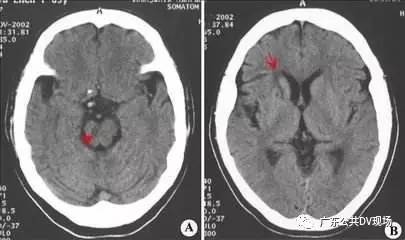

周围的人立刻将小李扶起,并迅速拨打了急救电话。救护车赶到现场后,医护人员迅速对小李进行了初步检查。检查结果显示,小李突发的是脑梗死,这是一种由于脑部血管阻塞导致的严重疾病。如果不及时治疗,后果不堪设想。

脑梗死,又称缺血性脑卒中,是由于脑部血管阻塞导致脑组织缺血缺氧,进而引发的一系列症状。根据专家介绍,脑梗死的成因有很多,包括高血压、高血脂、糖尿病、吸烟、饮酒等不良生活习惯,以及年龄增长、遗传等因素。